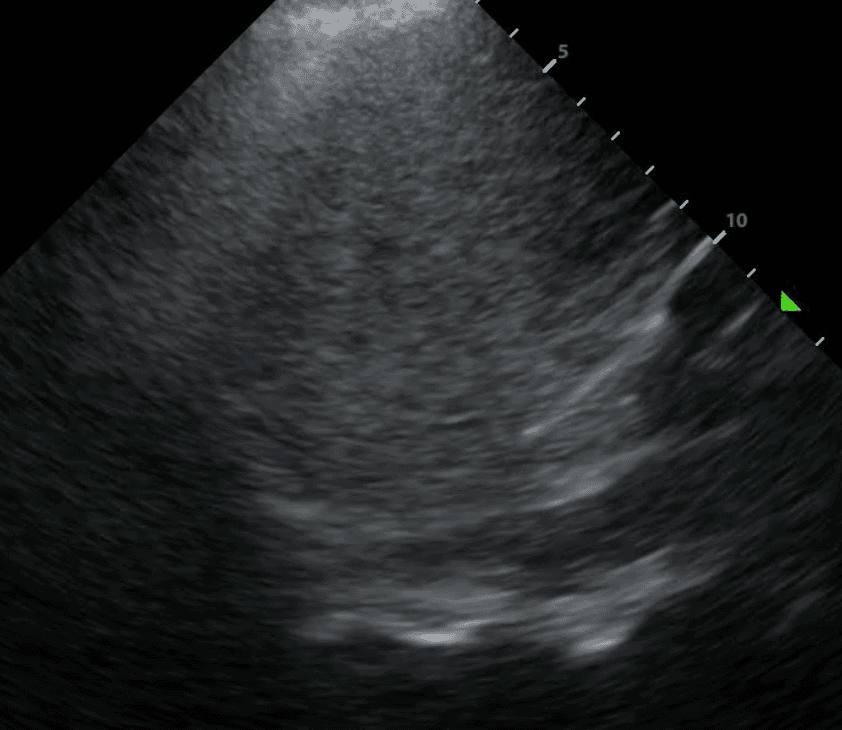

Finally, above the diaphragm, you will see one one of two things: if there are normal lungs without a pleural effusion, you will see an aerated lung obscuring the diaphragm during inspiration. This is referred to as a “curtain sign.”